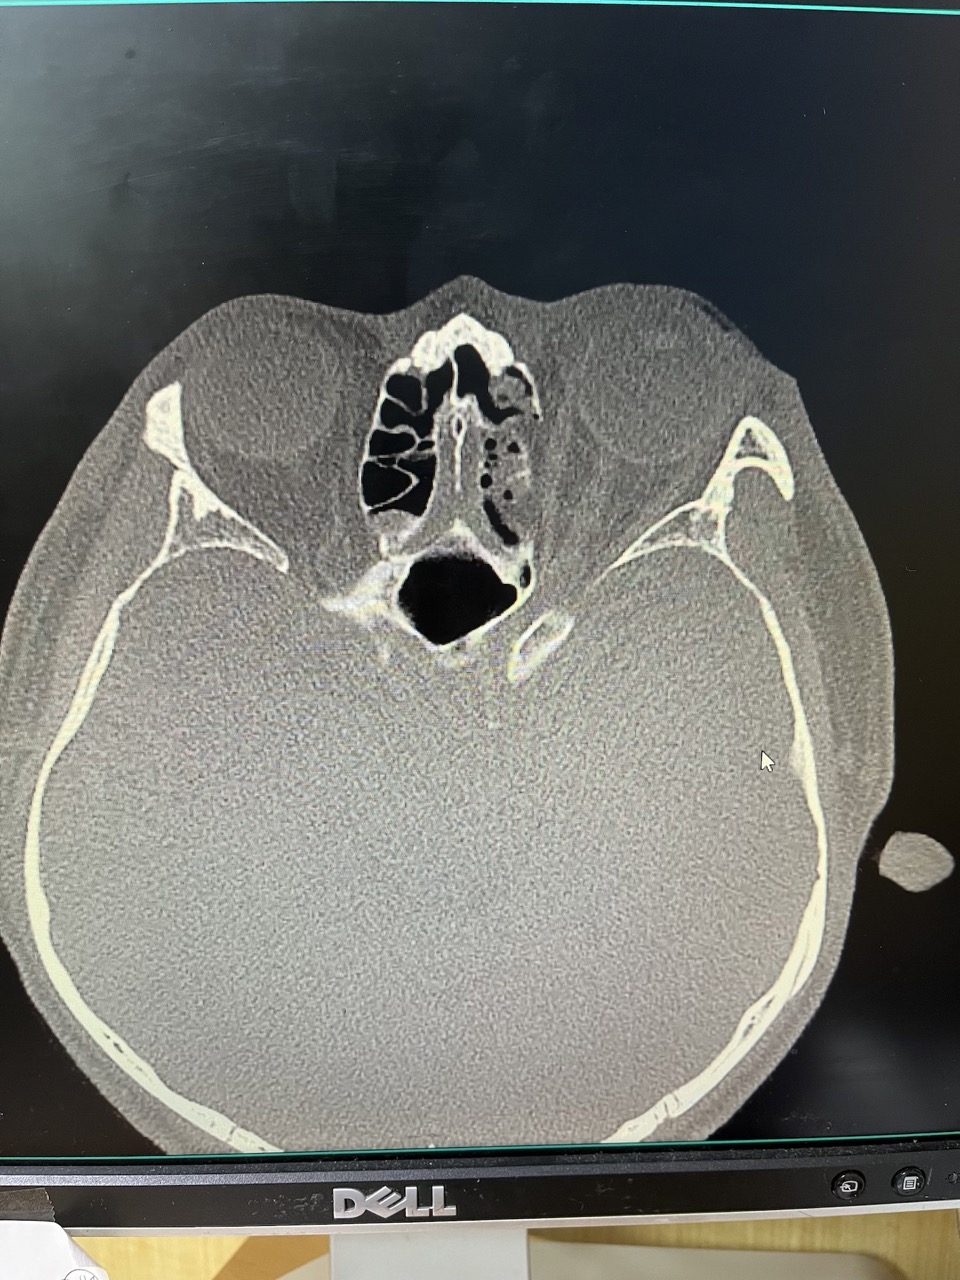

아래 제가 궁금한 사항입니다. 1. CT 사진 보셨을 때 안와골절 수술 여부에 대해 선생님 생각은 어떠신가요?

1. CT 사진 보셨을 때 안와골절 수술 여부에 대해 선생님 생각은 어떠신가요?

안와골절의 수술 적응증은 골절로 인한 증상이 없는 경우에 골절 크기가 내벽이나 하벽의 50% 이상으로 대략 잡고 있습니다.

첫번째 CT coronal plane 에서는 괜찮은듯 한데, 두번째 axial plane CT 에서는 50%를 넘어가는 듯 한데 애매하네요.

한달이 지나서 안구함몰이 없다면 앞으로 안구함몰이 생길 가능성은 희박하며, 보통 3개월이 경과해서는 더이상 진행하지는 않습니다. 지금은 수술에 대한 고민은 하지 않으셔도 될 듯 합니다.